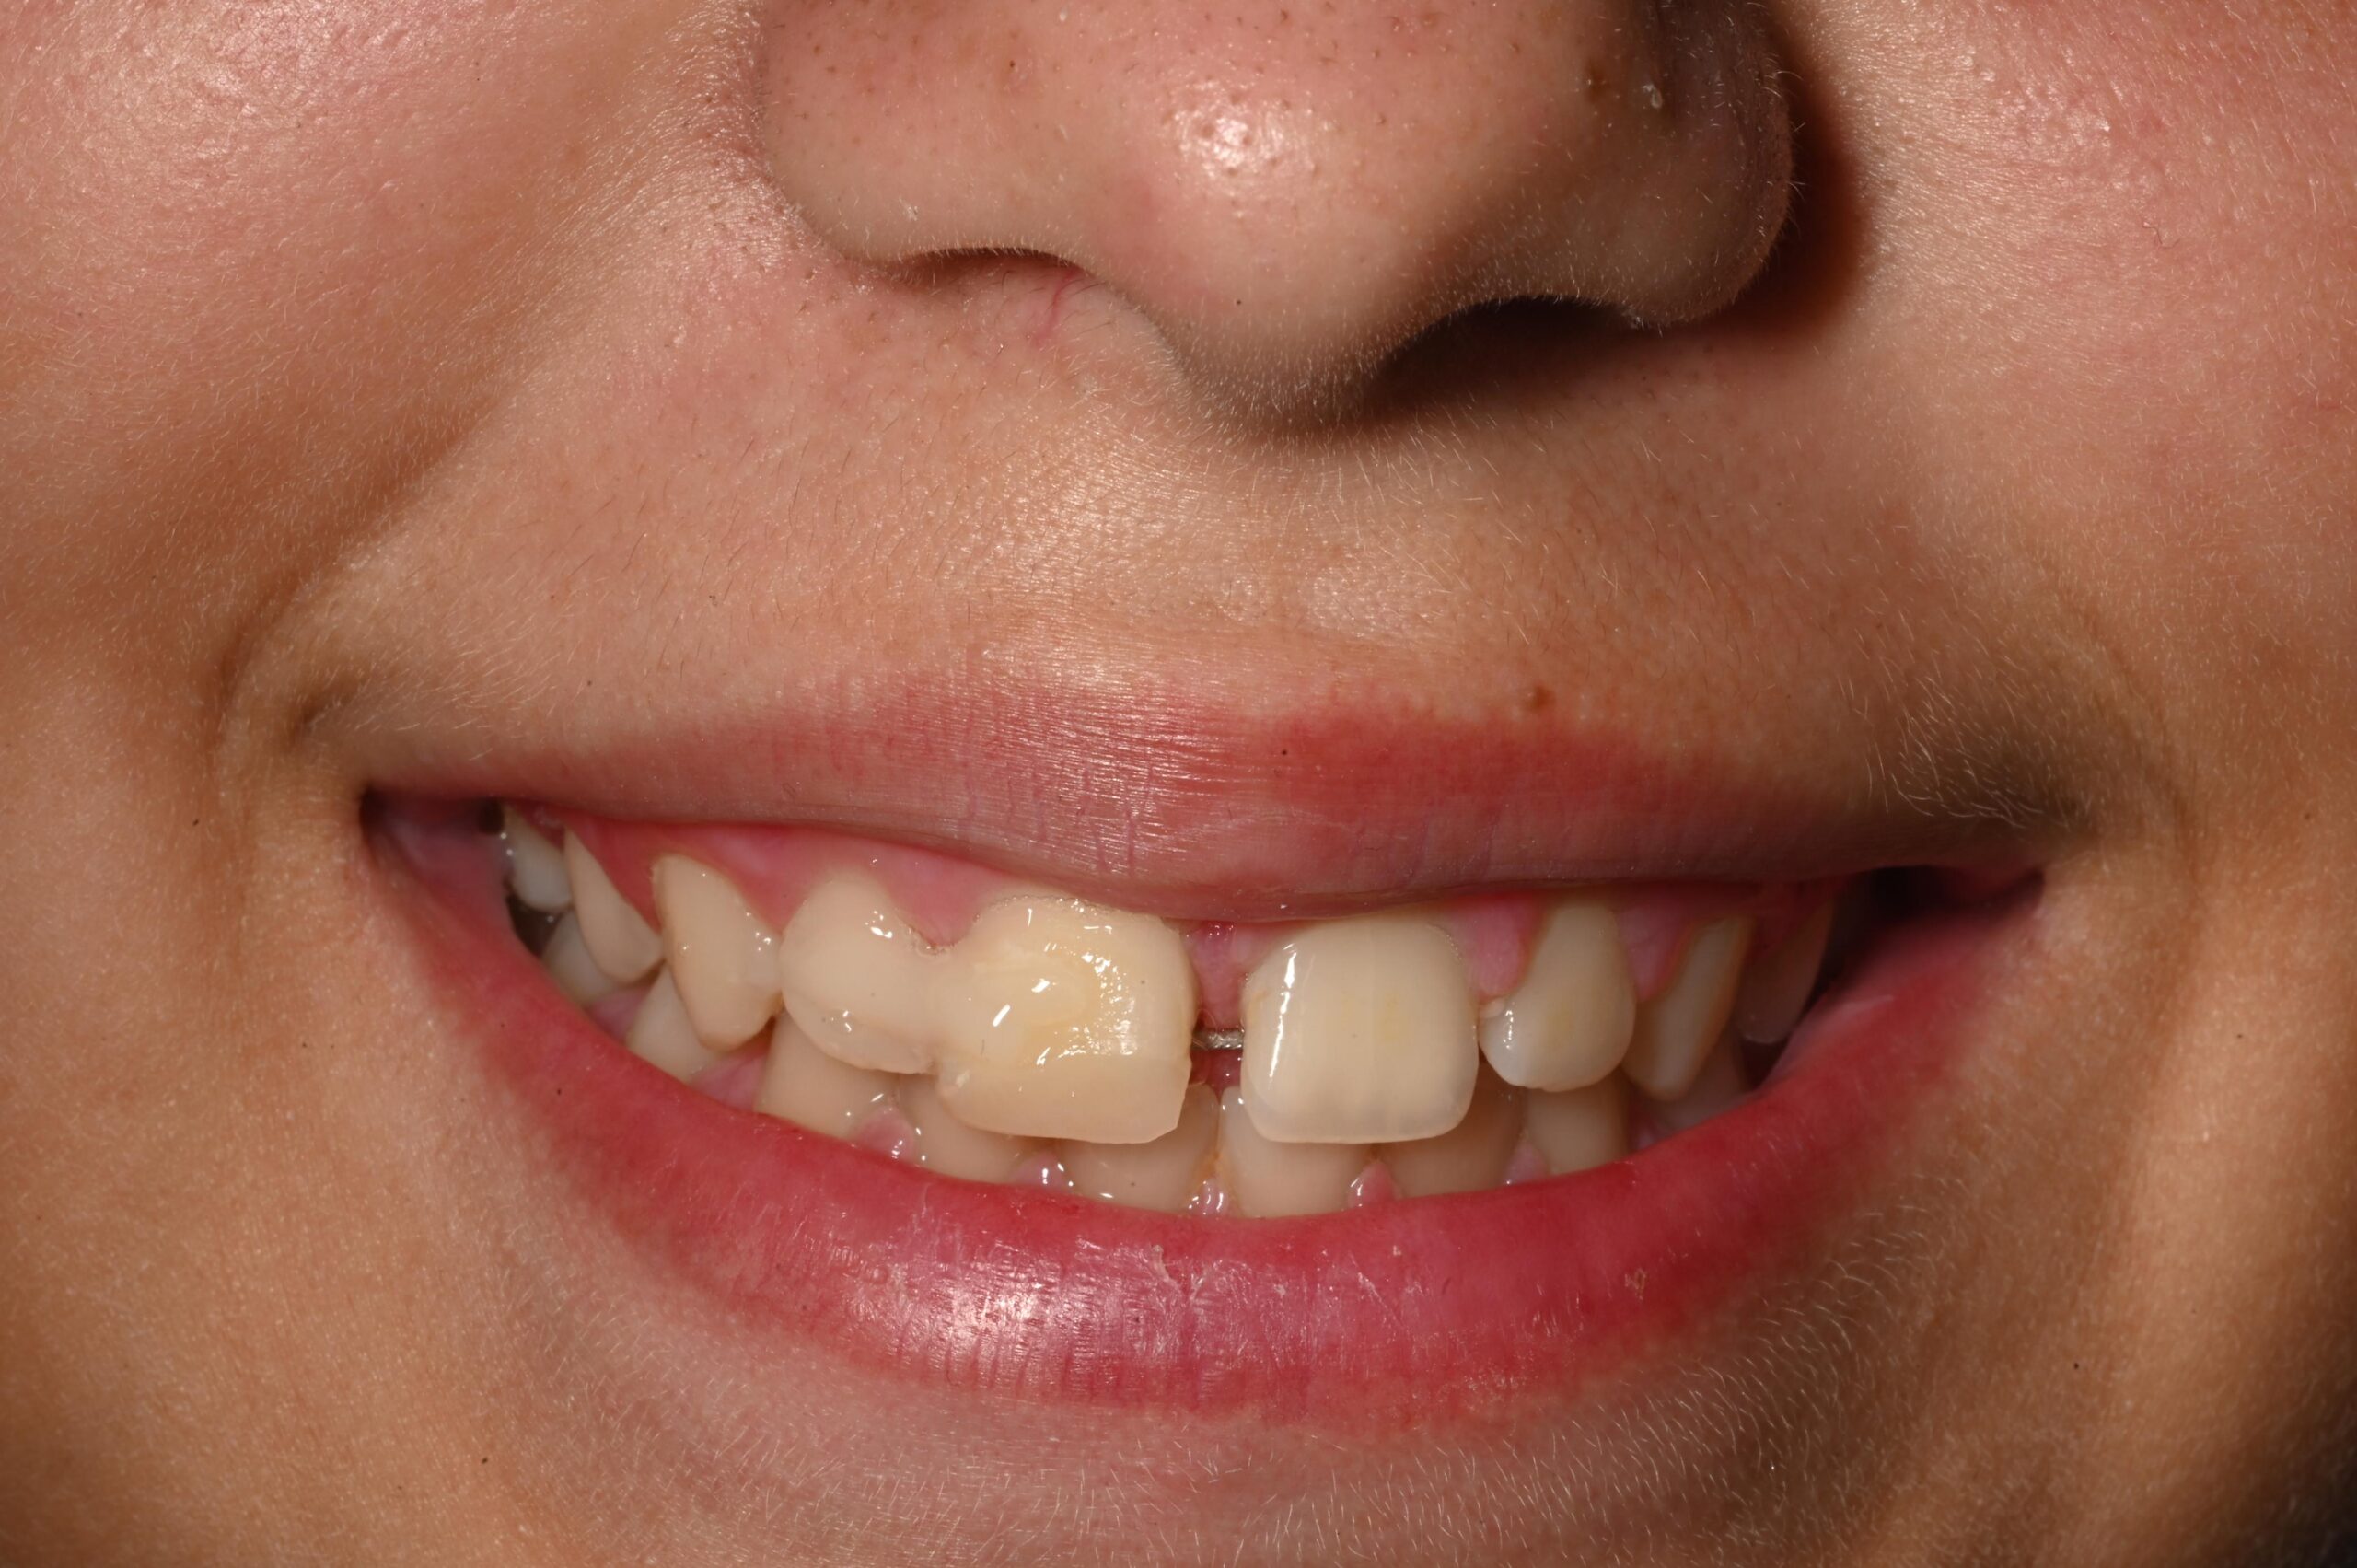

5. Përpunim estetik i kurorës

Pasi situata u stabilizua, Dr. Celami realizoi një korrigjim estetik për të rikthyer harmoninë e margjinales incizale të dëmtuar. Humbja prej 2 mm u kompensua përmes përpunimit estetik të kurorës, duke marrë parasysh moshën e pacientit dhe integritetin estetik të incizivëve.